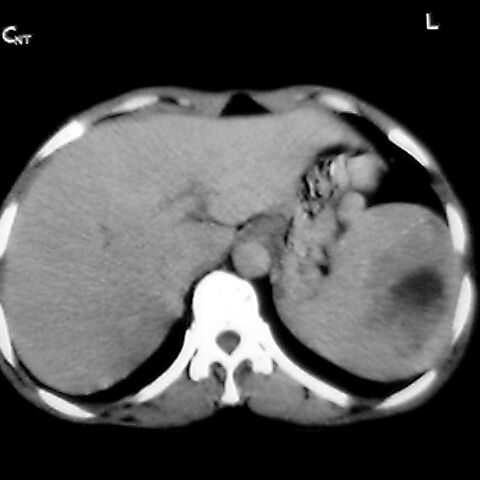

女 48岁 食道癌术前体检发现脾占位。

脾胀内部巨大低密度肿块,边界清或不清,中心坏死,轻度增强,内见散在钙化,结合食道癌病史多考虑:转移癌.

1肝右下叶小囊肿2右肾上极囊肿或错构瘤3脾脏不典型血管瘤可能性大.

脾脏低密度灶伴钙化,增强化明显,中心见液化坏死灶,强化延时明显。考虑血管瘤。转移瘤待排。